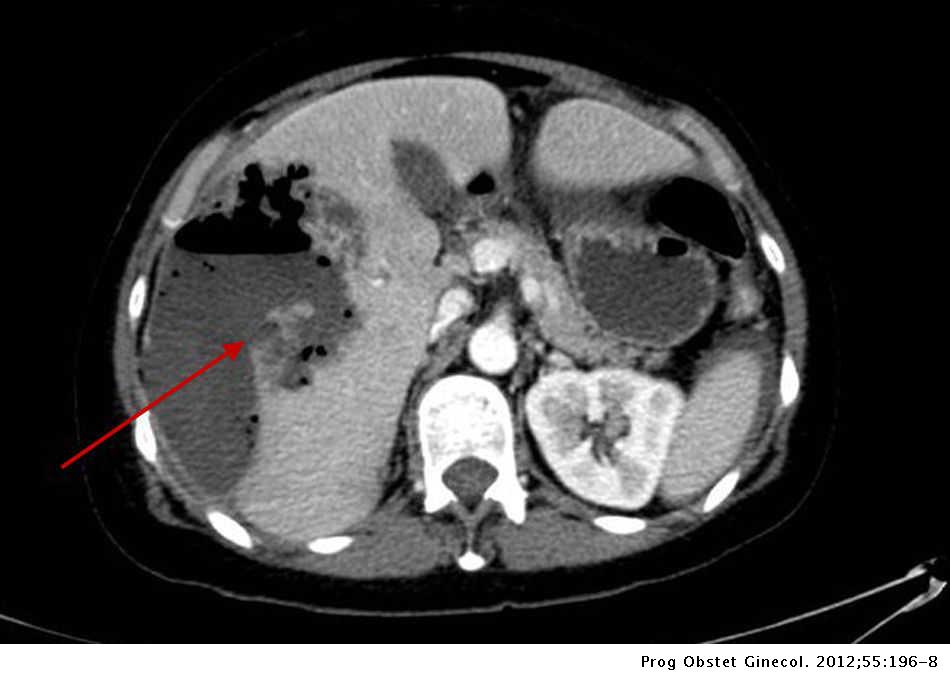

Absceso Hepatico Roto En Portadora De Dispositivo Intrauterino Progresos De Obstetricia Y Ginecologia